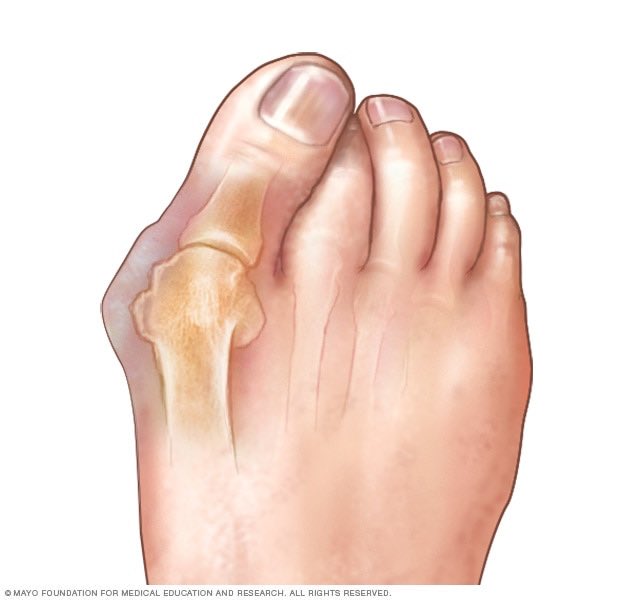

١-صعوبة ارتداء الأحذية؛ بسبب البروز العظمي في إبهام القدم.

٢-ألم عند البروز العظمي وماحوله.

٣-الضغط على الأعصاب المحيطة الذي قد يسبب ألمًا وأعراضًا أخرى.

١-اتجاه إبهام القدم للداخل نحو الأصبع الثاني،وحدوث بروز عظمي من الجهة الأخرى(السلامية العظمية)